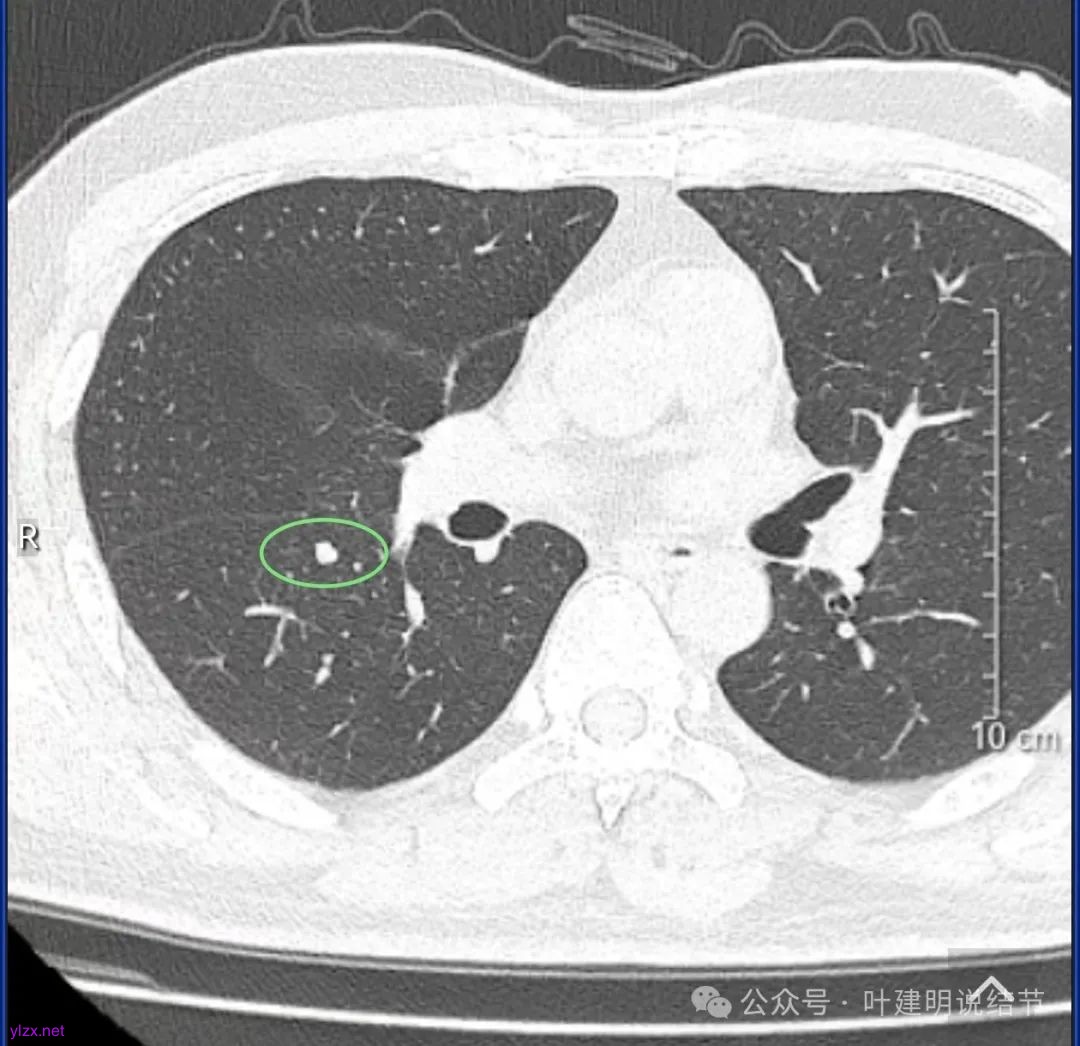

结友男性,41岁,具体病史记不得了,下面是请他重新发我的术前CT报告中截图的影像。

下叶背段有一实性结节,但没有找到其他磨玻璃结节。可以反馈的术后病理说下叶楔形切除了有个结节是肺泡上皮增生。大概不会是这处实性的,可能是很淡的,不容易找到的一处结节。算了,不管它。也不知道这处实性的有没有处理,还是不需要处理。

左下叶基底段淡磨玻璃结节,轮廓与边界清楚,考虑肺泡上皮增生可能性大。